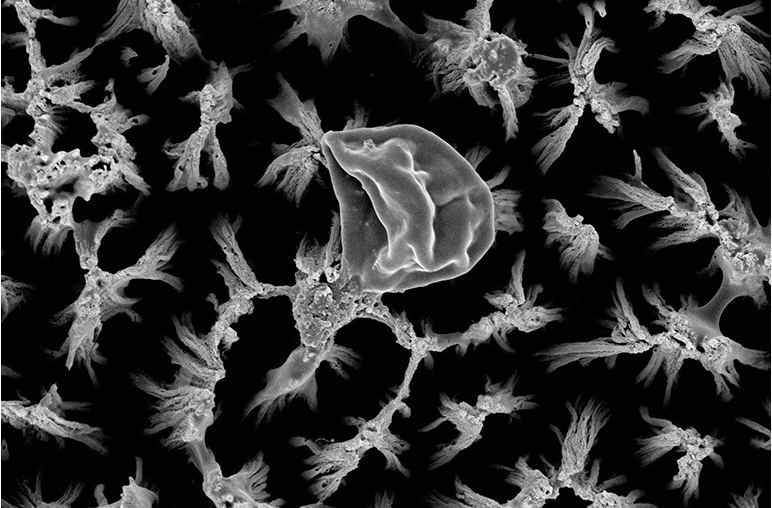

An intact Candida cell on polished titanium surface (left), and a ruptured Candida cell on the micro-spiked titanium surface (right).

They used a plasma etching technique to create tiny pillars on titanium, which is used in many medical implants. The tiny spikes are approximately the height of a bacterial cell, and when a cell settles on the surface, the spikes can lead to perforations in the cell that can cause its death. In studies so far, the researchers have shown that if the cell does not die outright, it will still perish a little later because of the damage it sustained.

While it is easy to visualize the antimicrobial activity as a simple skewering action, it is more like a stretching action, as the cells are pulled by different pillars. “It’s like stretching a latex glove,” said Ivanova. “As it slowly stretches, the weakest point in the latex will become thinner and eventually tear. This new surface modification technique could have potential applications in medical devices but could also be easily tweaked for dental applications or for other materials like stainless steel benches used in food production and agriculture.”